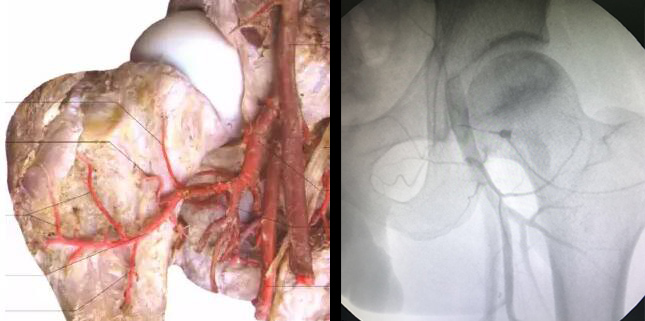

股骨头坏死症一度被认为是医学顽症,致残率高,严重影响着人们的正常工作与生活,给本该灿烂多彩的人生蒙上了一层灰色的阴影。但是,股骨头坏死虽是顽症并非绝症,很多患者只知其一,不知其二;在面临股骨头坏死治疗过程中左右为难,选择不清,治疗不慎,遭遇误诊误治、传统保守手术、盲目性治疗方式造成病情反复、加重,最终走向残疾。其实,随着现代医学的不断发展,保髋先融通创新理念、实践的深入研究,通过科学规范化诊疗,合理地选择适合的治疗方法,股骨头坏死患者是可以保住股骨头不需置换,达到功能恢复状态的。 如何突破传统治疗局限,解决保髋难题 股骨头坏死又称股骨头缺血性坏死,可因创伤(股骨颈骨折、髋关节脱位等)及非创伤(皮质激素、酗酒及血液高凝等)原因导致位于股骨头上下肢连接的三大供血动脉旋股外侧动脉、旋股内侧动脉、圆韧带动脉栓塞,引起供血不足、血运循环不良,造成股骨头骨细胞及骨髓成分死亡,继而导致骨质坏死、结构塌陷、下肢肌肉萎缩,从而引起疼痛、跛行、拄拐、瘫痪等一系列改变。学界公认治疗的前提在于打通堵塞的血管,如果股骨头坏死的血运没有打通,再多的药物无法通过血液到达股骨头内部,这就是为什么很多患者常年用药物却久治不愈的事实;另外,健康的骨质会因为血液不畅导致坏死塌陷,何况后天培养的骨细胞。所以说病虽在骨面,但究其根本还是在血液血管,融通才是最为关键的因素,当药物及营养进不去,代谢产物出不来,病情就会越来越严重。如何真正打通药物与营养供给通道,重建病灶处良性循环以及骨质的修复意味着功能的恢复,就成为重中之重,关乎保髋成败,然而融通看似简单,实则不凡。 如何规范融通才能达到良好保髋效果 据悉,血管融通后出现病情反复,在广州强直葆髋医院史东主任接诊的病例中并非个例,在3月份便有数十例,在当地医院或三甲综合医院做过血管融通术后又来院就诊的患者。很多患者会有这样的疑问,血管融通术作为保髋治疗股骨头坏死成熟的技术之一,被多家医院引进,治疗效果却参差不齐,有的患者融通之后还出现疼痛。>>>点击咨询,了解更多 为什么出现“同术不同效”?并非所有融通都是“可视血堵融通术结合血液净化”综合治疗 术业有专攻,专研有专长,概括来说有以下几点: 1、专项检查不够精准,属于哪一种淤堵类型?是哪一根还是几根血管发生血堵及堵塞程度?未做到精准的靶向疏通 2、虽然进行融通血管的治疗,但疏而不通,未完全清除积液、炎性物质,坏死组织等杂质容易造成二次淤堵,不仅股骨头外要清理,股骨头内更要创造良好环境,才有利于骨质生长 3、在骨质修复阶段,针对病情深层修复欠佳,包括血管壁修复、骨髓基质细胞植入等 目前,“可视血堵融通术结合血液净化”综合治疗作为保髋治疗的核心技术之一,在治疗早中期股骨头缺血性坏死患者取得了理想疗效,备受业界的关注和患者的信赖。很多医院奉行“拿来主义”,部分骨科医院的医生未经过系统化的专业培训,缺少“可视血堵融通术结合血液净化”综合治疗操作方面的临床经验。部分医院的医师认为血堵融通术仅仅是一项治疗的技术,严格来讲这是一种误解,规范的“可视血堵融通术结合血液净化”综合治疗是以疏通血管为核心的一系列微创技术的组合。部分医生在认识上的误区,并未做到专业治疗。 查的准,才能治得好!保髋治疗不可缺少一双 “电子眼” 可视血循分析、红外线热成像等特色诊疗方案,刷新诊断观念,将误诊漏诊风险降到最低 “治病必求于本”,只有明晰股骨头坏死发病根源,才能做到对症治疗。纵观患者整个治疗史,不难发现都存在着重治不重诊的现象,即血管堵塞查不明,关节腔炎性分布,患者体质分析等都会影响股骨头坏死治疗不的原因。 可视血循分析仪检查、红外线热成像仪检查等“电子眼”,可精准检测到股骨头病灶区哪一根血管堵塞了以及堵塞的位置、大小、栓塞的程度,定位炎性增生及堆积程度,指导医生依据专业的技术参数采取对症融通;对关节腔炎性粘连进行可视化微创清理,打通药物及营养供给通道;能够辨别患者属于中医9种体质中的某一种(一般综合医院骨科也难以辨别),从而进行针对体质差异,对应的中西医调理,起到抗复发效果,打破了常规检查不能辨别体质,导致千人一方的局面。 例如:股骨头缺血性坏死早期症状为髋关节偶有隐隐作痛,酸软无力,大部分患者可无症状。X片检查多为正常,CT扫描及磁共振检查有异常多表现为骨小梁模糊,矿化改变,可视血循分析检查可见股骨内血供不良、大转子区及旋股外侧动脉血供稍差。股骨头缺血性坏死I期坏死症状十分隐匿,一般只有经验丰富的专业医生才能通过磁共振及可视血循分析才能检查出来。>>>点击咨询,了解更多 对于股骨头坏死专业检查和治疗的要求则更为精细,而传统的检查多依靠医生的临床经验判断,因此专业医院引进“电子眼”等先进检查和治疗特色仪器,这一系列的科学化、专业化、规范化检测为后续的可视融通、骨细胞移植、骨质修复、整体治疗、避免复发提供了有力保障,避免误诊误治给患者带来伤害。 媒体报道、专业学术研讨令人瞩目 主持人赵忠祥对话骨科名医,“可视血堵融通术结合血液净化”综合治疗走进科教栏目,节目以深度解读股骨头缺血性坏死的保髋难题为重点,在传媒的号召下,通过专家访谈、医患互动等形式,加强各地股骨头缺血性坏死健康防治工作,并向股骨头缺血性坏死患者传达科学就医、规范诊疗之道,传递股骨头“保髋不置换”的重要前提。>>>点击咨询,了解更多 股骨头坏死中西医临床诊疗新进展“国医名师学术”研讨会上,国医大师唐祖宣指出:恢复供血,保髋先融通是早中期股骨头坏死患者治疗的难点。该观点也受到领导孙隆椿、李俊德及北京协和医院、北京友谊医院等专家的一致认可。因此,要想治好股骨头坏死就必须突破这一治疗难点,即保髋先融通,打通病灶处药物及营养供给通道,恢复微循环,重建良性循环。 探讨股骨头保髋不置换的前提:融通血管,恢复血运 [观看视频↑↑↑] 临床证实:科学诊疗技术是实现“保髋”的关键 “可视血堵融通术结合血液净化”综合治疗是目前医学界对股骨头缺血性坏死传统药物治疗以及手术不足而新研发的综合诊疗体系,是采用数字减影血管检查和微创先进技术相集而成的一种专门治疗股骨头缺血性坏死的微创治疗方法,揭开了保髋治疗股骨头坏死灿烂的新篇章。 —“可视血堵融通术结合血液净化”综合治疗 治疗实况↑↑↑— —效果直击 血管融通前后动态对比— 该技术是在可视影像设备导向下,通过毫米微针将溶栓及扩血管药物植入堵塞的动脉血管中,直接作用于堵塞的血管,使得血堵被融通,血供正常,再辅以多项专业微创技术(包括髓芯微减压术、自体细胞技术、体外冲击波电磁场技术等多功能技术重组)清理关节腔、修复坏死骨质,使得股骨头恢复正常生理功能状态,从而达到治痛以及保住股骨头不置换的治疗目的。股骨头坏死特色诊疗技术和模式,以实实在在的口碑信誉、突出贡献和成绩,造福广大股骨头坏死患者。